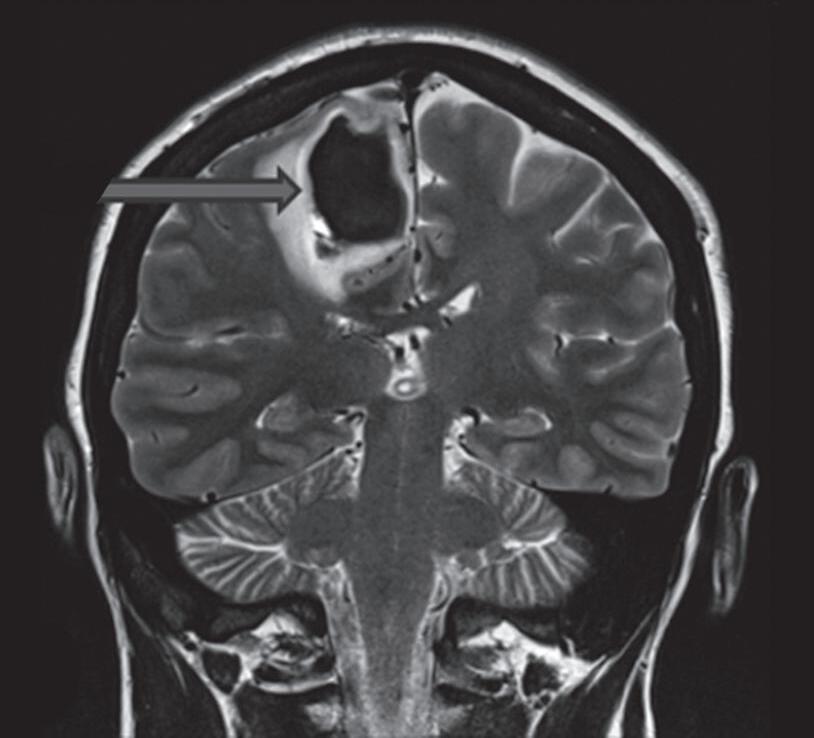

Fig. 1-14. RNM encéfalo, T2 axial (a) e coronal (b), demonstrando MAV grau 2 no lobo parietal esquerdo.

Arteriografia cerebral (c) AP e (d) em perfil, demonstrando a irrigação pelos ramos da artéria cerebral média (ACM) e anterior (ACA), com drenagem pela veia de Labbé, no seio transverso sigmoide.